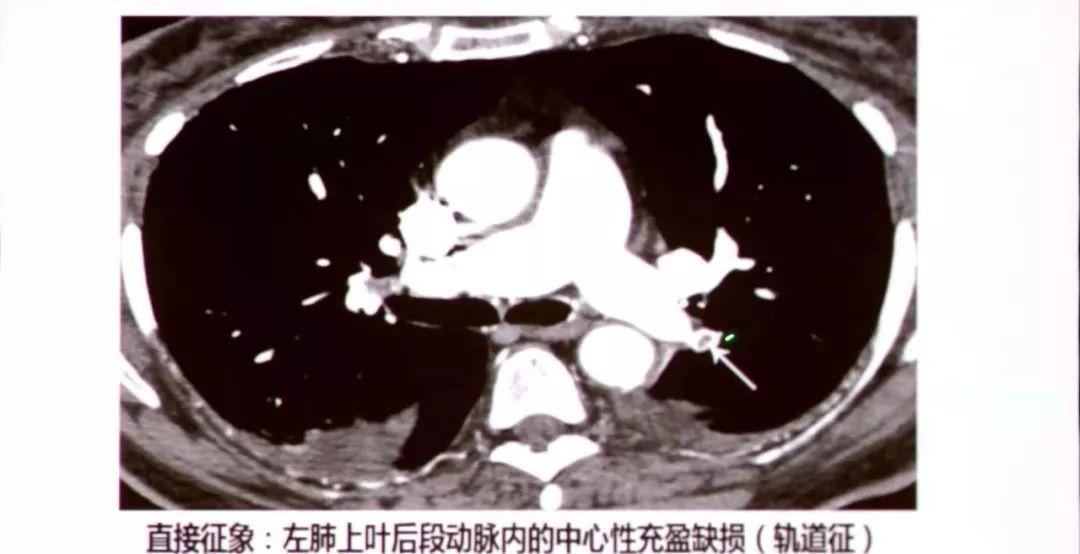

左肺上叶尖段肺动脉栓塞,闭塞,轨道征

附壁充盈缺损;3.完全闭塞;4."轨道征"即心充盈缺损;5.